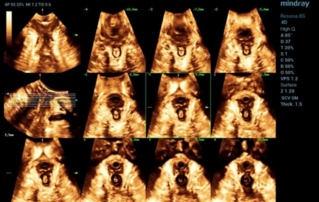

?? ?? ?? ??? ?? ?? ?? ???? ?? ???? OBG ?????? ?????. ?? ??, ?????(CNS) ??? ?? ?? ??? ?? ? ?????. ???? ?? ??? ?? ??? ??? ??? ?? MSP? 2D ????? ?? ???? ?????. ??? ?? ?? ? ??? ??? ???? ?? ???? ? ????.